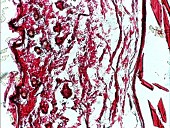

不同穴位的胶原纤维分布:Masson染色法中可以看出,不同穴位胶原纤维的分布有明显的不同,以足底部最多。